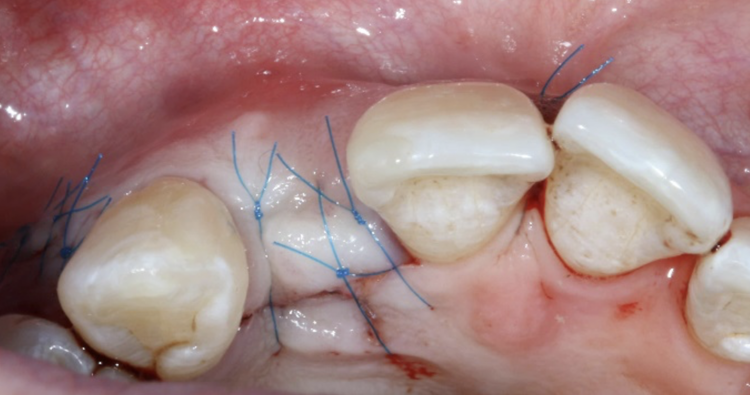

The second surgery involved a palatal crestal incision and a full thickness flap elevation revealing good turnover of bone graft into host bone. A bone level implant was placed in an appropriate three-dimensional position completely surrounded by new bone and no additional bone grafting was required. A 4mm healing cap was placed.

A free gingival graft was taken from the palate below the upper right molar teeth and the epithelium was removed on the surgical table. The connective tissue strip of graft was then placed on top of the healing cap (and suspended over the healing cap) and secured to the palatal flap with 6.0 PGA Resorba Sutures. Finally, the buccal flap was closed with complete primary intention wound healing using 6.0 Prolene.